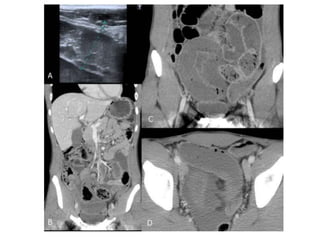

El estudio de Tomografía por

Computadora tiene una sensibilidad

del 80 al9 0 %

HALLAZGOS:

 Dilatación proximalde intestino

 Descompresión distalde intestino

 Contraste intraluminalque no pasa

más allá de la obstrucción

 Intestino distal con poco gas

•La presencia de asa intestinal en

forma de U o de C indica obstrucción

de asa cerrada

•Neumatosis intestinal

,gas en la

vena porta,opacidad mesentérica y

captación deficiente del contraste

intravenoso en la pared hace pensar

en estrangulamiento

El estudio deTomografía por Computadora tiene una sensibilidad del 80 al9 0 % HALLAZGOS:  Dilatación proximalde intestino  Descompresión distalde intestino  Contraste intraluminalque no pasa más allá de la obstrucción  Intestino distal con poco gas

•La presencia deasa intestinal en forma de U o de C indica obstrucción de asa cerrada •Neumatosis intestinal ,gas en la vena porta,opacidad mesentérica y captación deficiente del contraste intravenoso en la pared hace pensar en estrangulamiento